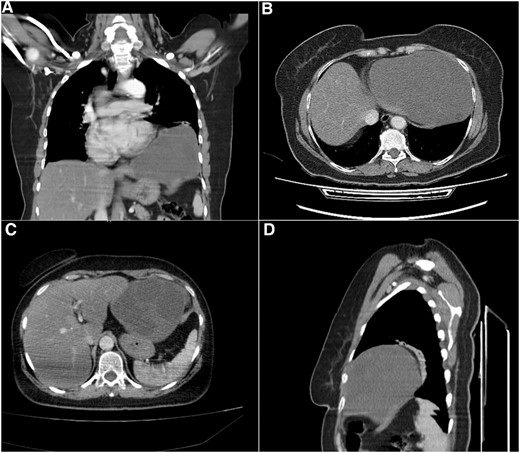

Computed tomography (CT) scan showed a cystic formation containing varying densities. The cyst size was 15 × 13 × 12 cm with an ambiguous location involving the left lower thorax and the left hypochondrium, with a direct bordering of the pericardium and the left hepatic lobe (Fig. 1).

Computed tomography (CT) scan. (A) Coronal section, shows the cystic formation in the left hemi-thorax. (B) and (C) Axial section, shows the borders with the pericardium and the left hepatic lobe. (D) Sagittal section, shows the limited posterior extension of the cyst.